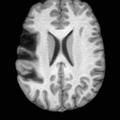

Pathology-to-Healthy Editing. Fig. 5 (a) presents comparison results on four input brain images with lesions of varying sizes, shapes, and densities. All competing models, although specialized for healthy brain image synthesis, struggle to reconstruct pathological regions, especially near lesion boundaries. In contrast, USB accurately reconstructs the corresponding healthy brain, even in challenging cases with large, high-density lesions where normal brain structures are almost completely obscured (last row). Tab. 2 provides a quantitative comparison for pathology-to-healthy editing, where USB achieves the best performance across all three datasets, demonstrating the effectiveness of its unified framework in reconstructing healthy brains from pathological inputs. Additional results are in Suppl. B.

Healthy-to-Pathology Editing. As shown in Fig. 5 (b), given a healthy brain image paired with a random lesion mask, USB seamlessly embeds the lesion into the healthy anatomy, producing realistic pathological appearances consistent with surrounding structural context. Yet UNA’s syntheses are visually unrealistic, with the conditioned lesion mask simply overlaid as a parallel layer onto the healthy brain. Tab. 3 further demonstrates USB’s superior performance. The evaluation was conducted on 100 pairs of lesion masks and healthy brains, with real stroke images

(a)PathologicalInput ImageSynthSR [18]Brain-ID [28]UNA [30]USBHealthyGround TruthRefer to captionRefer to captionRefer to captionRefer to captionRefer to captionRefer to captionRefer to captionRefer to captionRefer to captionRefer to captionRefer to captionRefer to captionRefer to captionRefer to captionRefer to captionRefer to captionRefer to captionRefer to captionRefer to captionRefer to captionRefer to captionRefer to captionRefer to captionRefer to caption(b)HealthyInput ImageConditionalLesion MaskUNA [30]USBRefer to captionRefer to captionRefer to captionRefer to captionRefer to captionRefer to captionRefer to captionRefer to captionRefer to captionRefer to captionRefer to captionRefer to captionRefer to captionRefer to captionRefer to captionRefer to caption

Figure 5: Comparison of bidirectional brain editing. (a) pathology-to-healthy, the circles and arrows highlight lesion regions and unsuccessful reconstructions; (b) healthy-to-pathology. Note that SynthSR and Brain-ID cannot perform healthy-to-pathology editing.